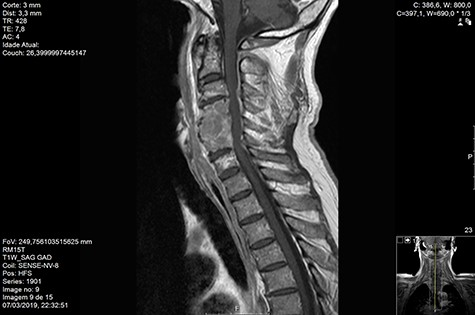

Computed tomography (CT) (Figs 1–3) and magnetic resonance imaging (MRI) (Figs 4–6) of the cervical spine were performed and revealed a lytic lesion involving most of C4, C5 and C6 vertebral bodies with bilateral extension to the posterior spinal elements of C4 and C5 and complete disruption of C4-C5 and C5-C6 intervertebral discs.

The Spinal Instability Neoplastic Score (SINS) [4, 6, 7] for assessing spinal instability from metastatic disease was used and the lesion was deemed unstable (SINS 13), with impending risk of increased neurological damage.

Findings from laboratory tests (serum protein electrophoresis) led to the diagnosis of MM. The patient was placed on a Philadelphia c-spine collar and underwent local 3D external-beam radiotherapy (20Gy in five fractions).